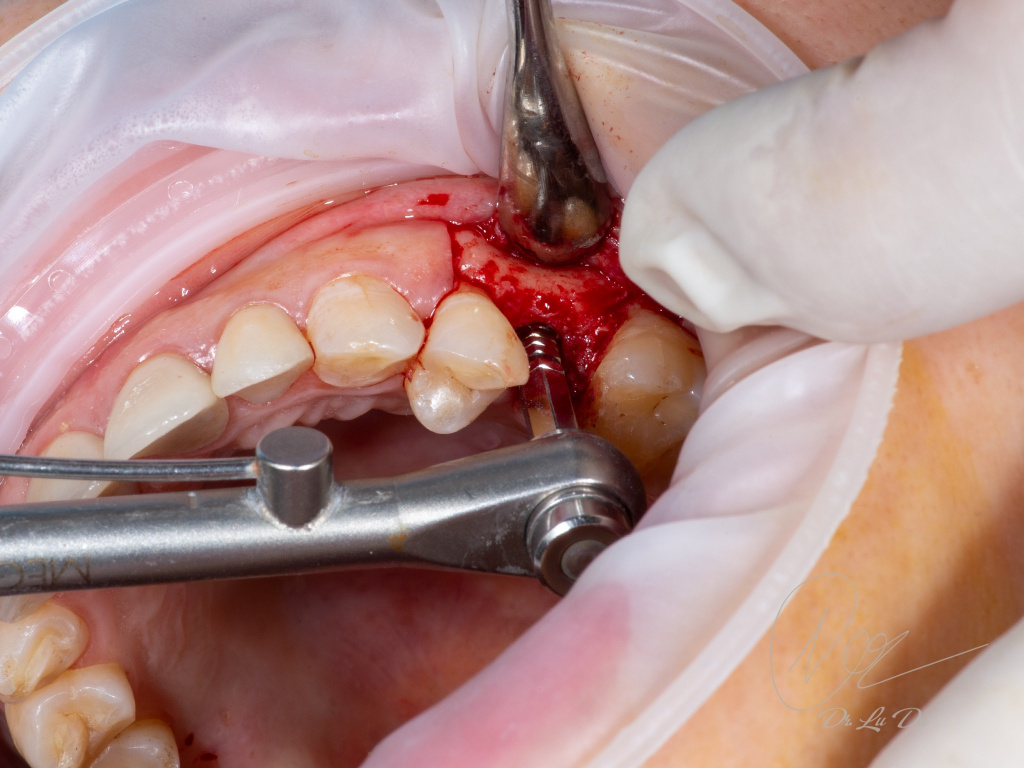

Имплантация AnyRidge с двусторонним закрытым синус-лифтингом.

Осложнения: правосторонний гайморит.

Кейс MINEC: Dr Lu Du